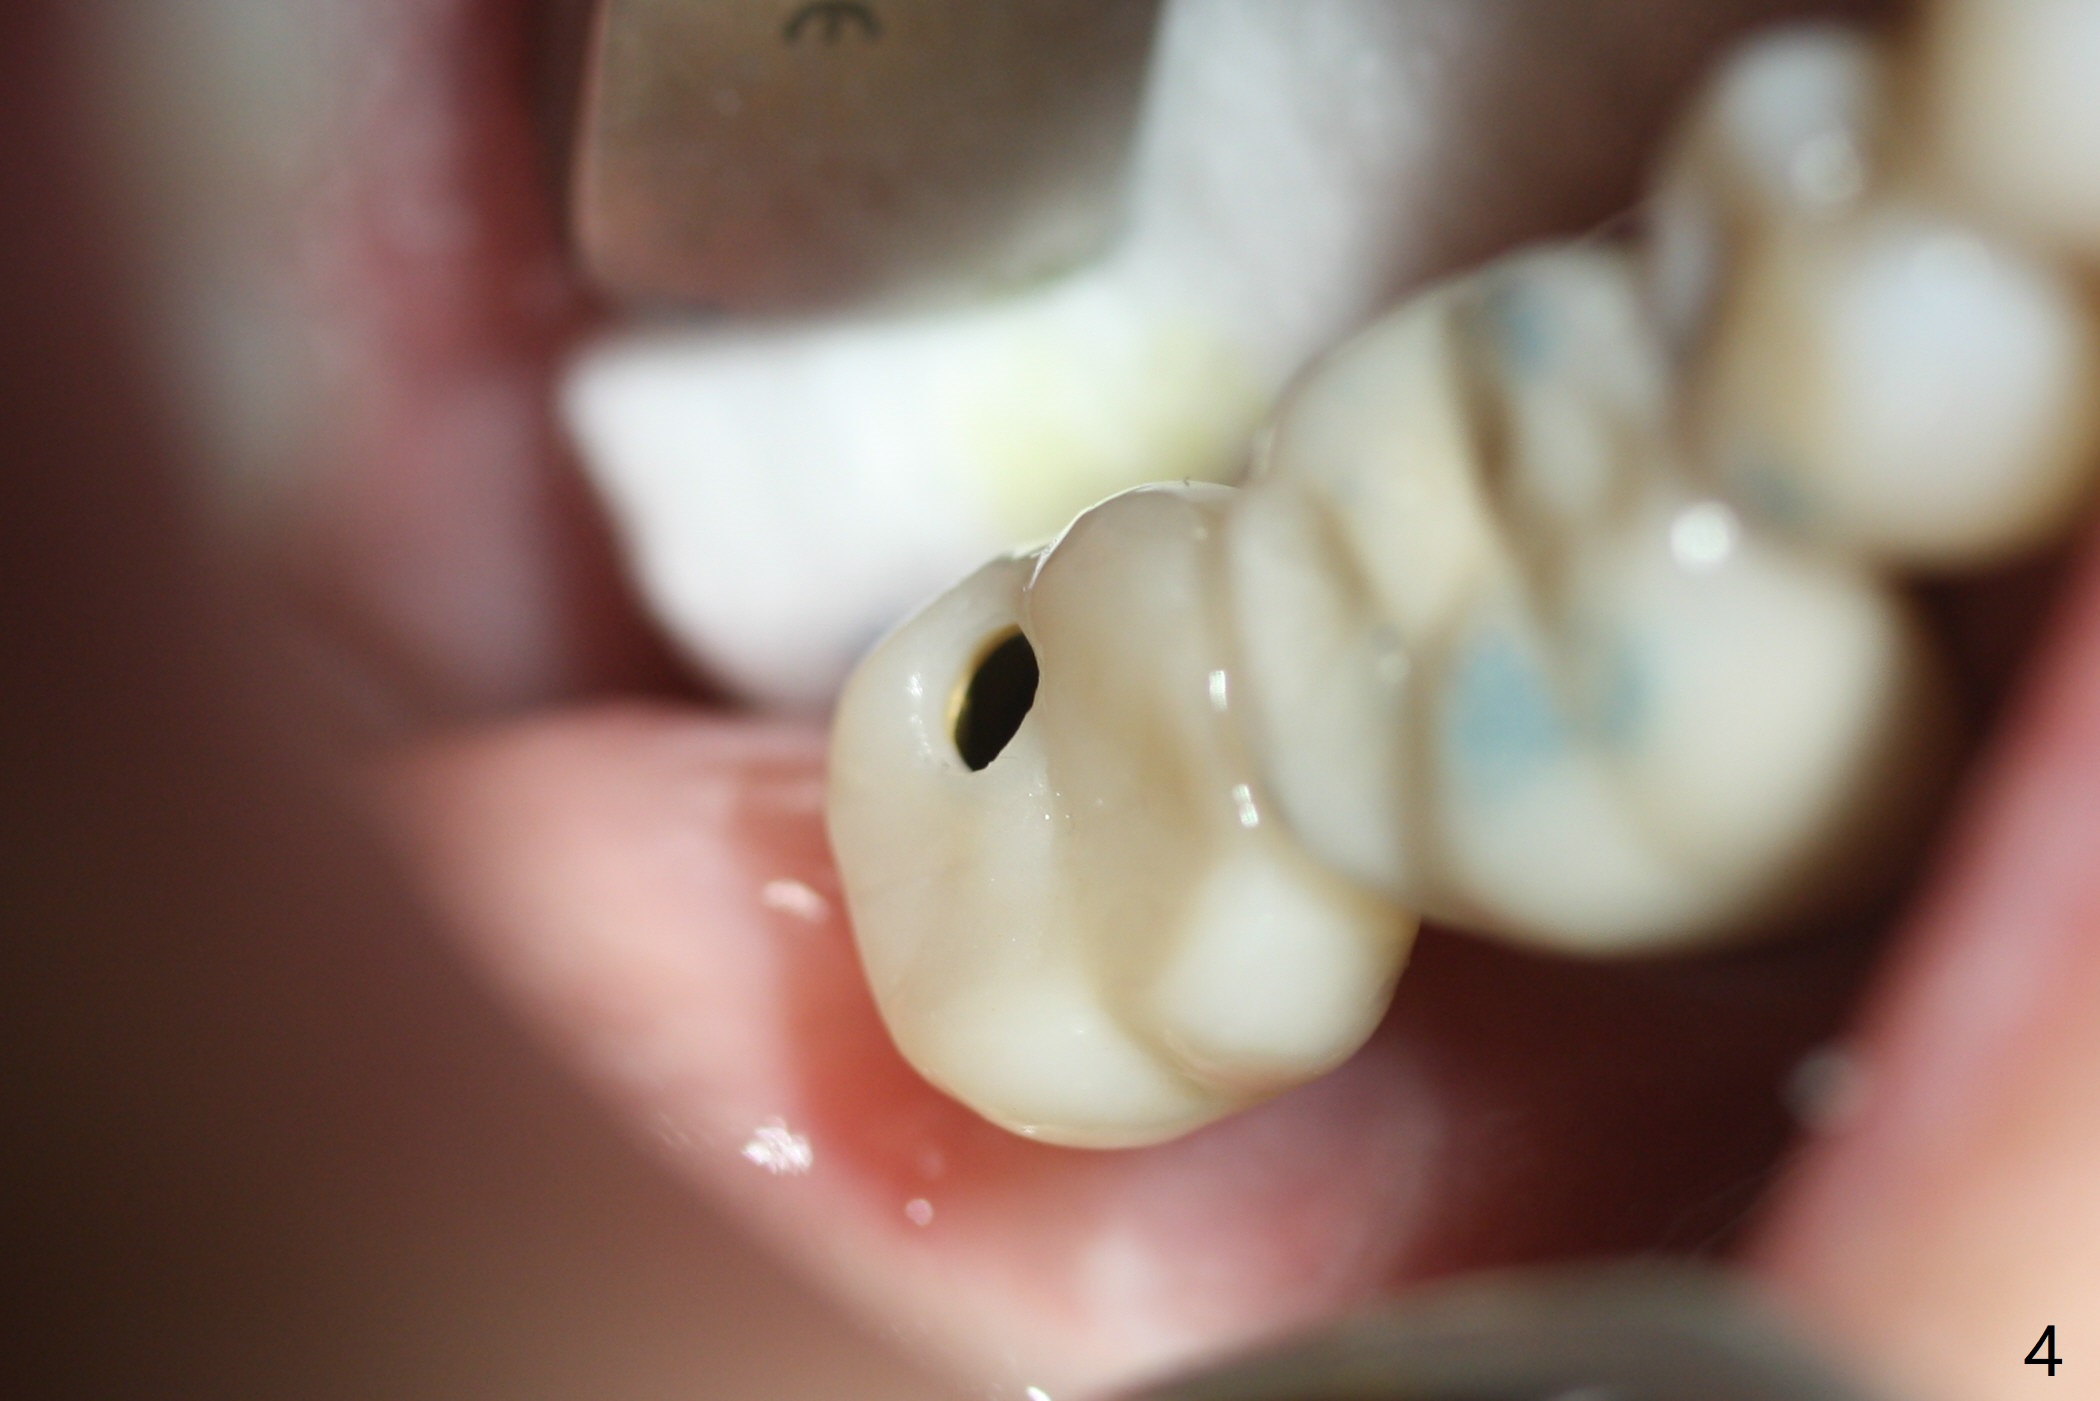

The implant, apparently having been osteointegrated 5.5 months postop (Fig.3), was placed deep, probably related to pressing the distal end of the guide too heavily.  It is difficult to take impression with use of a 5.2x5.5(5) mm abutment.  The access hole is distolingual (Fig.4).  The abutment screw has increased chance of loosening.  Cross bite at #31 is related to the lingualized access hole (Fig.5,7).  It is essential to check the occlusion clinically and in the lab prior to guide design.  Immediately post cementation PA confirms the implant distal placement (Fig.6).

The trajectory is not right, since no matter how the sensors are placed, the implant threads cannot be shown clearly (Fig.10), in consistence with the distolingual access hole (Fig.11).